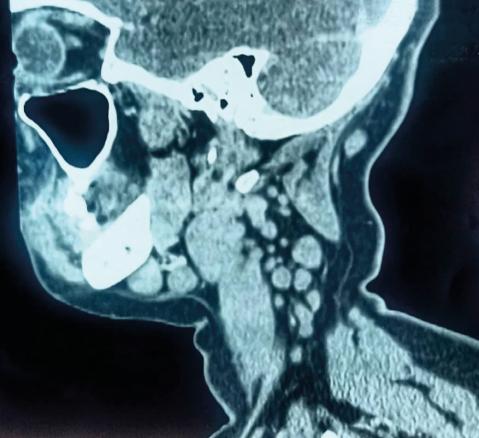

Une patiente âgée de 40 ans est admise à l’hôpital pour exploration d’adénopathies cervicales. L’interrogatoire révèle une obstruction nasale chronique accompagnée d’une rhinorrhée. L’endoscopie met en évidence une rhinite croûteuse avec un bombement du cavum (fig. 1). La tomodensitométrie montre un cavum pseudotumoral (fig. 2, 3 et 4). L’histologie objective un processus granulomateux tuberculoïde (fig. 5). Le GeneXpert sur fragment de biopsie, l’intradermoréaction à la tuberculine et la recherche de bacille de Koch dans les crachats sont négatifs.